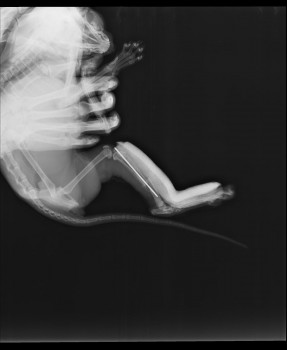

История закончилась хорошо. Кость срослась, спица в ней никак не мешает движению и не дала осложнений.

На снимке - состояние через 80 дней после операции.

Хочу отметить, что в Подольске все клиники используют только метод остеосинтеза спицами. Если перелом со множеством осколков, то фиксировать их лучше другими методами, то есть придётся везти животное в клинику в другой город.